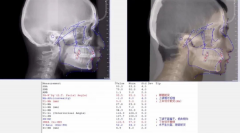

想要安全放心健康的矫好牙,正畸术前检查要重

通常患者到医院做矫正时,医生都会问,有没有拍片检查过。有些患者感到疑惑...【详细】